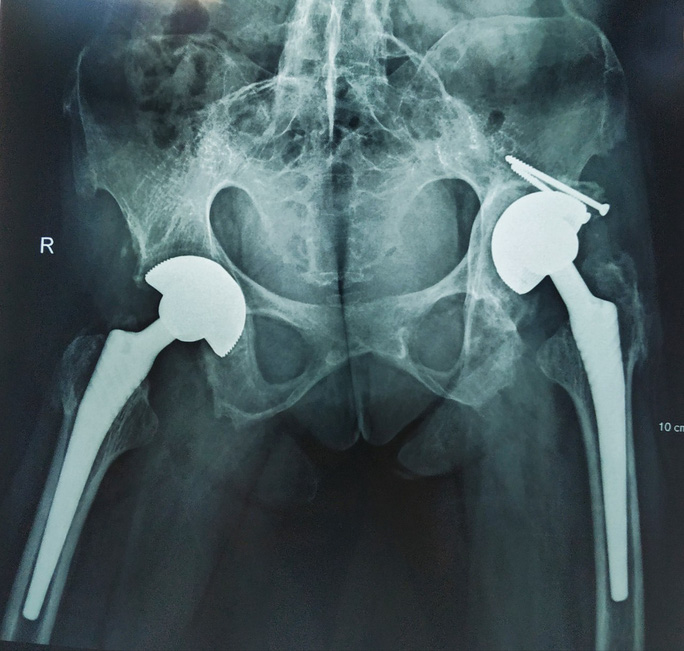

Tiến sĩ - bác sĩ Ngô Bá Toàn, Phó trưởng khoa Phẫu thuật Chấn thương chung, Bệnh viện Việt Đức, cho biết bà H. bị bệnh viêm cột sống dính khớp từ nhỏ, khi đến bệnh viện, bà đã có biểu hiện biến chứng viêm dính khớp cột sống và viêm dính cứng khớp háng, bà không thể ngồi và bước đi được.

"Chúng tôi nhận định ca phẫu thuật cho bệnh nhân H. rất phức tạp bởi hai khớp háng của bà đã có biến chứng viêm dính biến dạng, thêm nữa tình trạng viêm trong máu thường xuyên ở mức cao dễ dẫn đến chậm liền vết thương thậm chí nhiễm trùng sau mổ. Trước tình trạng của bà, các bác sĩ đã hội chẩn đa chuyên khoa kỹ lưỡng và đưa đến quyết định phẫu thuật thay khớp háng 2 bên bằng kỹ thuật mổ ít xâm lấn với khớp hai chuyển động chống trật và chống mài mòn"- bác sĩ Toàn nói.

Điều may mắn là ngay sau mổ, sức khoẻ bà H. ổn định, hồi phục tốt và được nhân viên y tế hướng dẫn tập phục hồi chức năng sớm. Khoảng 1 tháng sau phẫu thuật thay khớp háng, bà H. đã có thể đi lại bình thường và được hướng dẫn tiếp tục tập luyện để có thể bình phục nhanh. Bệnh nhân chia sẻ đây là niềm hạnh phúc mà trong suốt 30 năm chiến đấu với bệnh tật, bà không dám mơ tới một ngày nào đó bà lại có thể đi lại nhẹ nhàng, vững chắc trên mặt đất bằng chính đôi chân của mình.